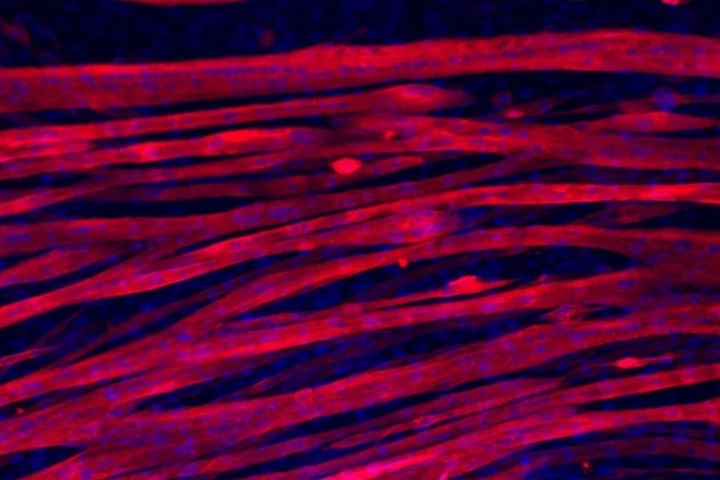

Growing muscle for lab-based testing is a tough process, and previous attempts to do so – making use of plastic scaffolds – have failed to produce fully-formed muscle fibers. Now, a team from USC has taken a different approach, using a water-logged gel, or “hydrogel,” as a scaffold.